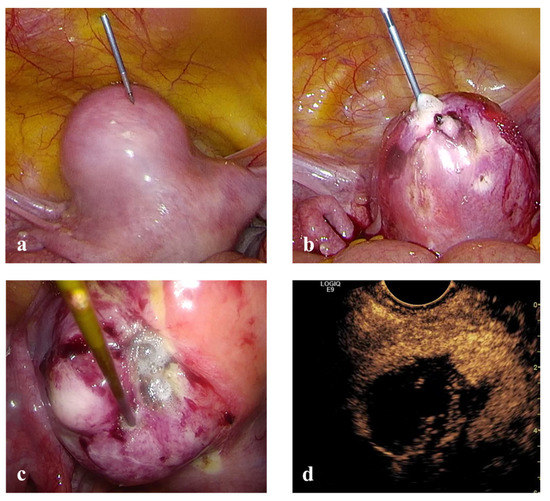

Laparoscopic RFM: general anesthesia, dorsal position, standard laparoscopic instrumentation and transvaginal ultrasonography for intra-uterine needle guidance (Figure 3).

Figure 3. (a) RF electrode inserted directly into the abdomen without the aid of any trocar. (b) and (c) RF ablation of uterine myomas under laparoscopic control. (d) Intra-operative trans-vaginal CEUS during Laparoscopic RFM.